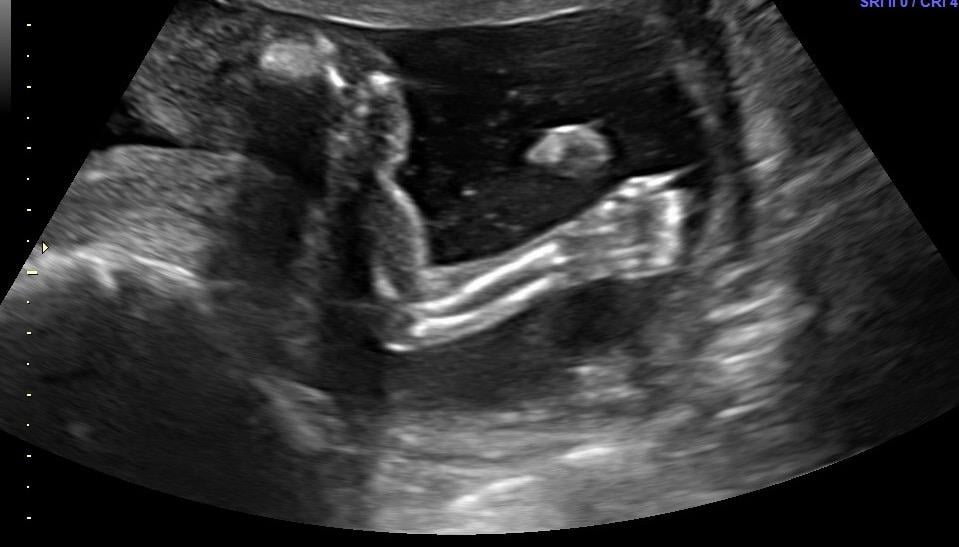

Hoping this works-ive never uploaded on here from a phone. This is sweet baby at 17+5 for our anatomy scan. We aren't finding out sex, so still using interchangeable pronouns and avoiding calling the baby "it". Babies nickname has been Batman since the beginning (cause....why not). Since we didn't get a great face shot to do measurements, I get to go back in 8 weeks for another. Which I am secretly thrilled about. This picture is SUCH a change from babies first photo shoot at 5+6!